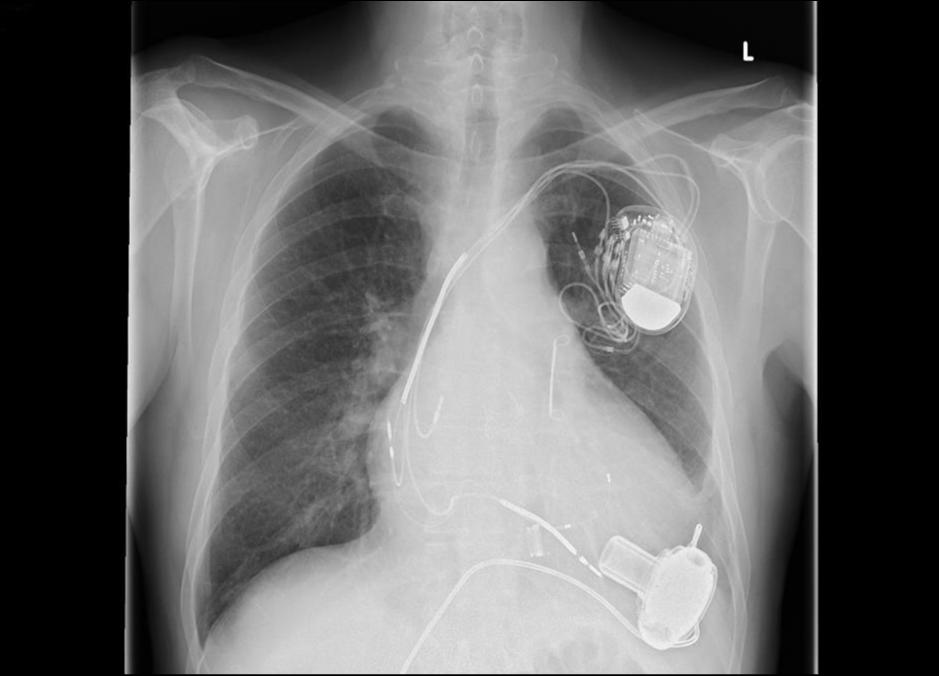

2022年10月14日,福建省药械联合采购中心发布《心脏介入电生理类医用耗材省际联盟集中带量采购公告(第1号)》。

根据采购公告,电生理类医用耗材集采联盟成员,包括福建、河北、浙江、广东等在内的27省(区、市),规模堪比“国采”。

心脏电生理市场,是为数不多的进口替代尚未攻破的器械堡垒之一。

根据弗若斯特沙利文报告,2020年中国电生理器械市场的前三名均为进口厂商,其中,强生以30.30亿元销售额独占58.8%的市场份额;

其次是雅培和美敦力,分别占比21.4%和6.7%,三者合计市场份额超过85%。国内选手中占比最高的是惠泰医疗,但市场份额仅有3.1%;微创电生理等选手,位置则更加边缘。